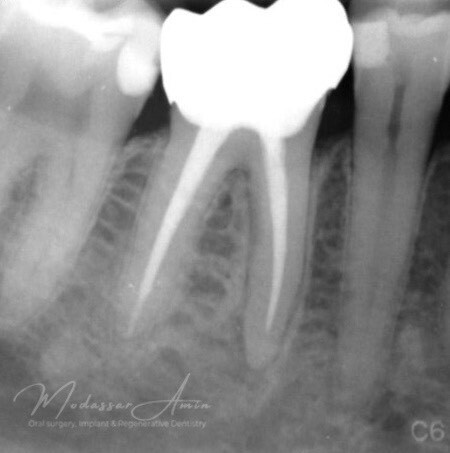

PATIENTFALL

"Pasienten presenterte med tann 46 som ikke kunne bevares grunnet en dyptgående infraksjon inn i furkasjonen. Forholdene lå til rette for en immediate implantatbehandling. Ved hjelp av Versah osseodensifikasjonsbor ble det interradikulære beinet ekspandert på en skånsom og forutsigbar måte, noe som ga høy primærstabilitet (>40 Ncm) til tross for en lokal bendefekt apikalt mesialt etter kronisk apikal periodontitt. Den gode stabiliteten muliggjorde bruk av SSA (Sealing Socket Abutment) for forsegling. På grunn av tynn bløtvevsfenotype bukkalt ble behandlingen supplert med bindevevstransplantat (CTG)"

Kontrollröntgen för verifikation